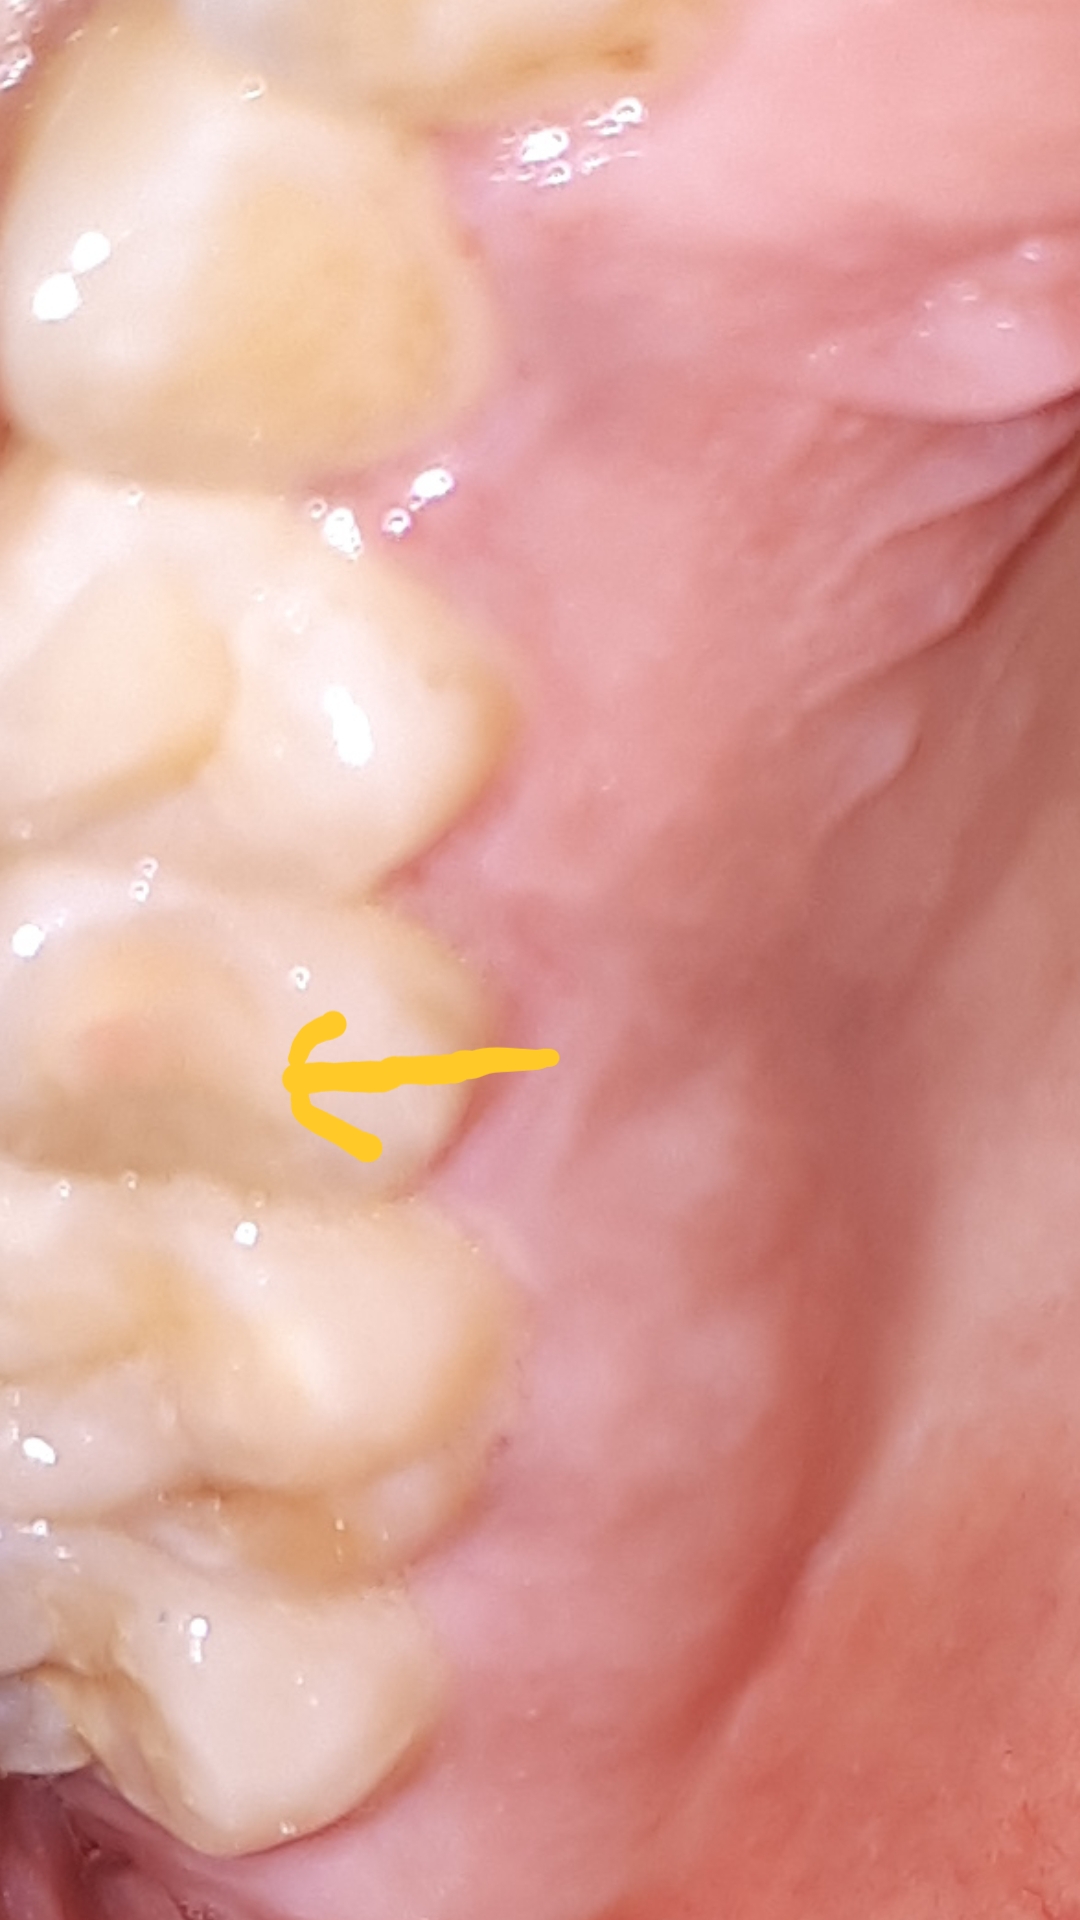

Author: Soullessammy Posted: di, 08/07/2018 - 12:41 weet een van jullie wat dit kleine rondje betekent die kies is soms ook wat gevoelig Attach vV nee... ik verwijs toch echt nee... ik verwijs toch echt naar de tandarts. Stuur privébericht Login of registreer om te reageren di, 08/07/2018 - 13:07 Permalink Soullessammy Als antwoord op nee... ik verwijs toch echt door vV nee... ik verwijs toch echt Het was blijkbaar me wortel kanaal behandeling kiesje... mijn fout, sorry Stuur privébericht Login of registreer om te reageren di, 08/07/2018 - 13:13 Permalink 107 weergaves

Soullessammy Als antwoord op nee... ik verwijs toch echt door vV nee... ik verwijs toch echt Het was blijkbaar me wortel kanaal behandeling kiesje... mijn fout, sorry Stuur privébericht Login of registreer om te reageren di, 08/07/2018 - 13:13 Permalink